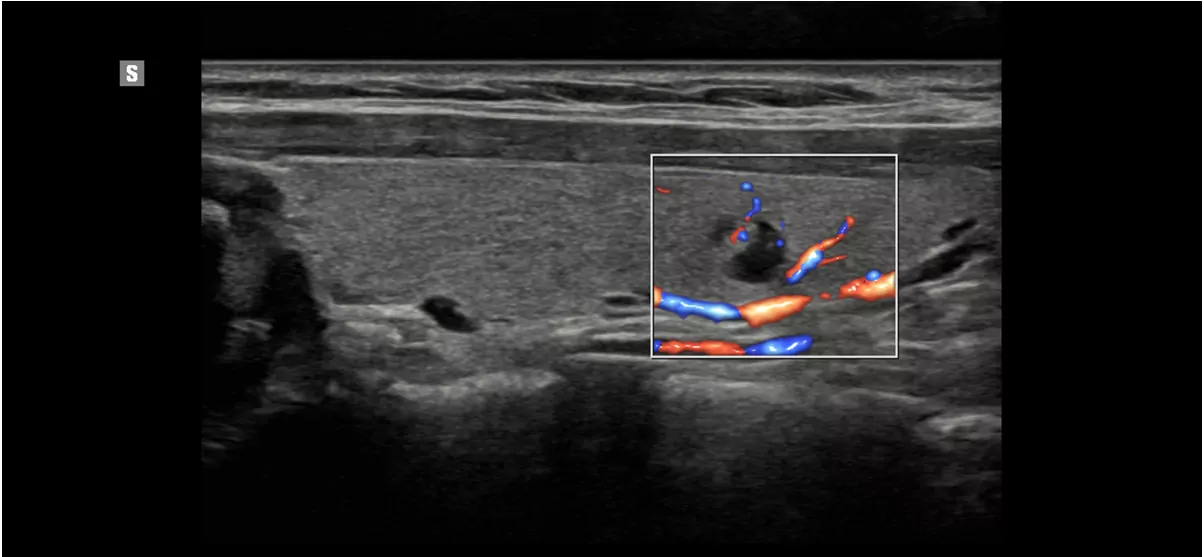

S-Flow™ технологія спрямованого енергетичного доплера може допомогти виявити навіть периферичні кровоносні судини. Це дозволяє поставити точний діагноз, коли дослідження кровотоку особливо складне.

Сухожиля пальців з S-Flow™